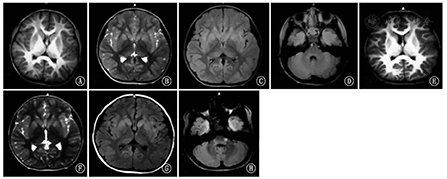

例2,男,初次就诊于北京大学第一医院年龄为5岁。就诊时主要症状:(1)癫痫发作,1岁9个月~3岁出现,共4次,表现为头后仰,双眼凝视,口角歪向一侧,四肢强直,最长持续20 min,均伴发热。(2)运动障碍,4岁时出现走路不稳,腿软,不愿行走。上呼吸道感染后下肢运动功能障碍加重,之后可慢慢好转。病程中多次出现发作性加重现象。(3)认知功能无明显倒退。就诊时查体:头围48.5 cm。颅神经(-);运动系统:呈自动体位,肌力、肌张力正常。病理反射(-)。既往史:3个月抬头,8个月独坐,12个月说简单话,15个月独走。家族史(-)。末次随访时患儿5岁7个月,运动功能有所提高,可以跑、跳,但易疲劳;认知功能正常;5岁6个月时癫痫发作1次,不伴发热;尚未出现吞咽困难、饮水呛咳等症状。MRI显示双侧岛叶及基底核T2WI及T2FLAIR稍高信号,4岁与5岁无明显变化;5岁时脑桥近左侧桥小脑角部位新增T2FLAIR高信号病灶(图2)。GFAP基因测序发现尚未报道的新生杂合突变c.262 C>T(p.Arg88Cys)。

A〜D :4岁时头颅MRI;E〜H :5岁时MRI ;A、E :T1加权像;B、F:T2加权像;C、D、G、H:T2液体衰减反转恢复序列图像A-D:the brain MRI from patient 2 at 4 years old; E-H:at 5 years old; A and E were pictures of T1 weighted imaging; B and F were T2 weighted imaging;C, D, G and H were T2 fluid attenuated inversion recovery imaging